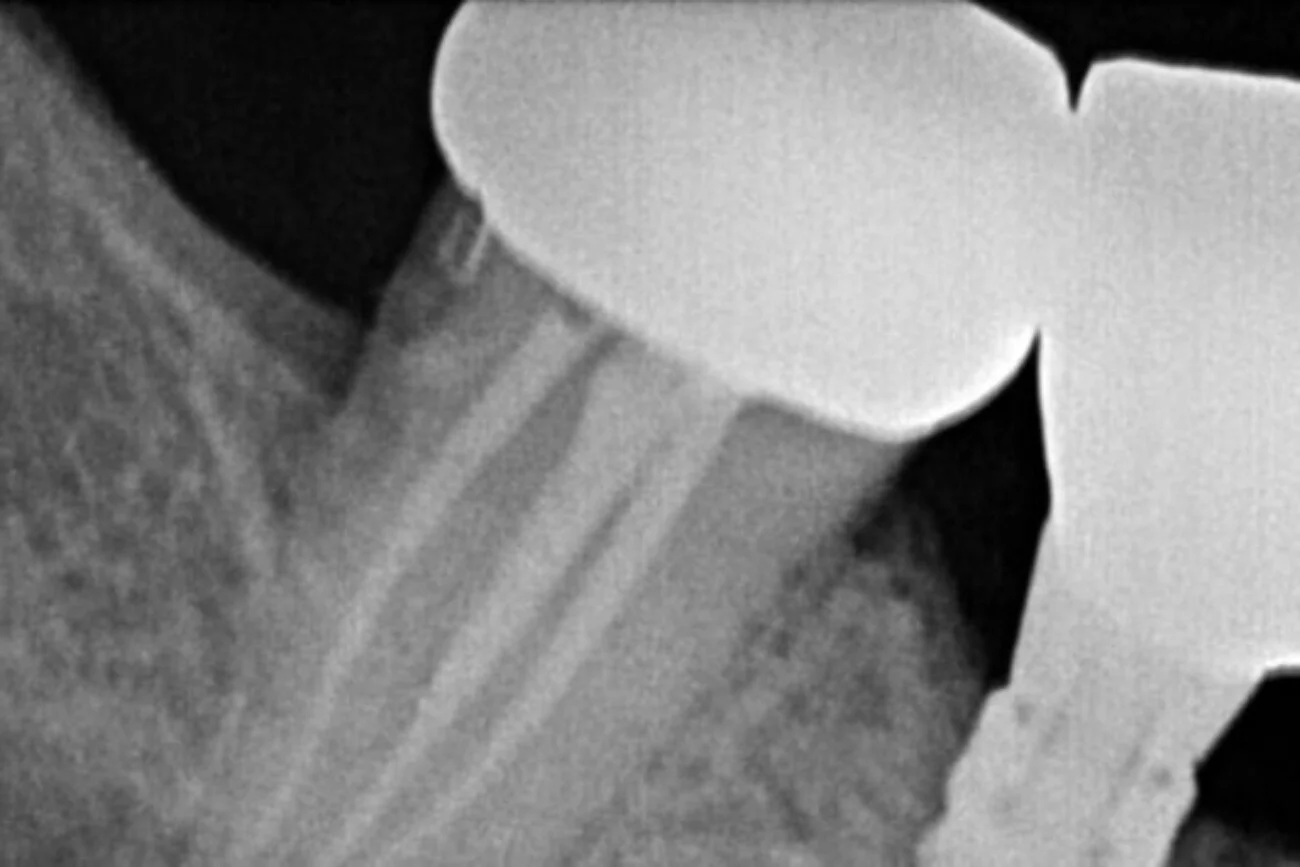

CAD/CAM (Computer-Aided Design/Computer-Aided Manufacturing):

Allowing for the precise design and creation of dental restorations, including crowns post-root canal. This technology ensures a custom fit and optimal functionality for restored teeth.

3D CBCT for Teeth Scanning:

Providing detailed 3D images of the teeth and surrounding structures. This aids in diagnosing complex root canal cases by offering a comprehensive view, enabling precise treatment planning.